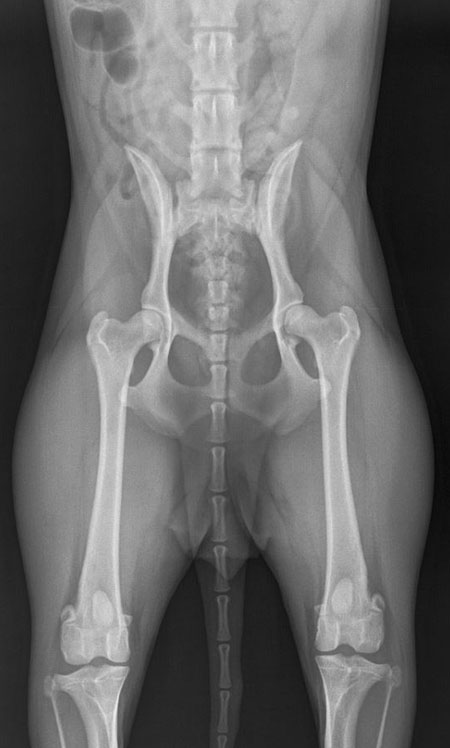

Hips Whoopee